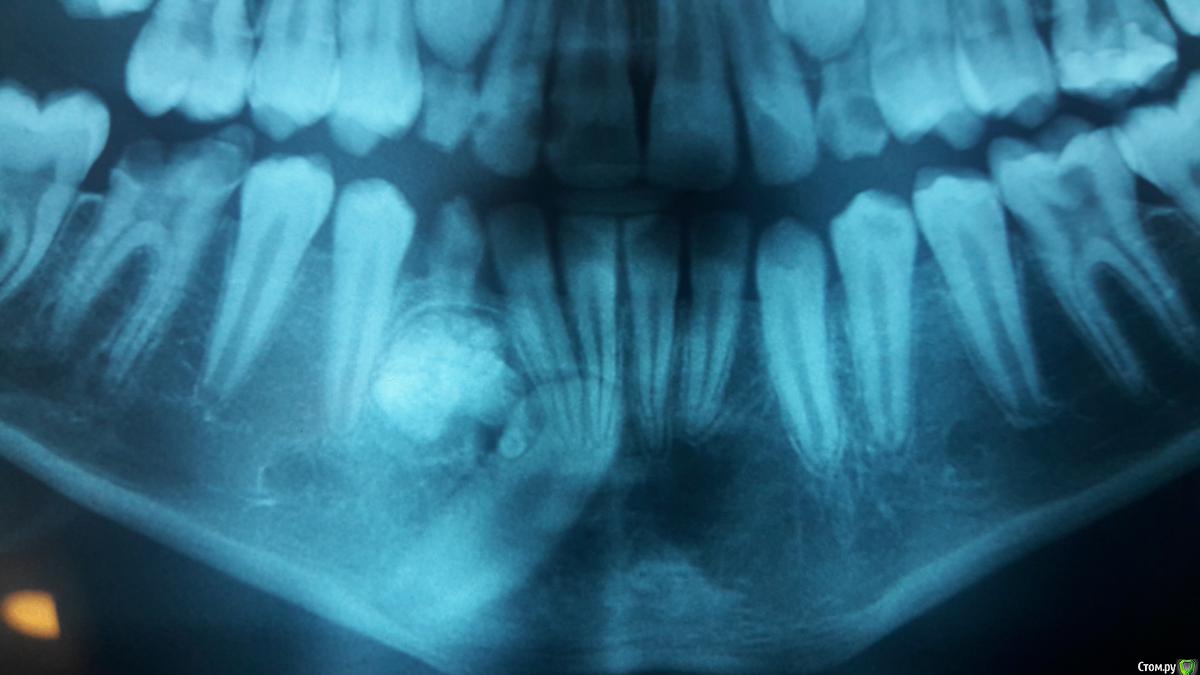

bilal Опубликовано 26 июля, 2018 Поделиться Опубликовано 26 июля, 2018 здравствуйте. как вы думаете что за образование под молочным клыком? одонтома?и как с ней поступать? 43 реально ли вытащить? Ссылка на комментарий

Дмитрий Л. Опубликовано 26 июля, 2018 Поделиться Опубликовано 26 июля, 2018 (изменено) Одонтома или цементома или (...) покажет гистология. В этом возрасте рост опухоли приостанавливается. Лечение одно - удаление. Я бы за молочный клык не боролся. Разве что он никак не связан с новообразованием и корень просто отклонён кзади. КТ смотреть надо или по ходу операции решать. Непонятна линия просветления которая к резцам идёт. Артефакт, свищ, секвестр? Кт бы...А ещё там куча кариеса На счёт ортодонтии 43 смотреть КТ надо, его тут сильно размыло из-за особенностей оптг. Изменено 26 июля, 2018 пользователем Дмитрий Л. Ссылка на комментарий

Bier Опубликовано 27 июля, 2018 Поделиться Опубликовано 27 июля, 2018 Если клык вестибулярно, то вытащить вполне реально. У нас был 1 в 1 такой случай. К сожалению не запротоколирован. В итоге все выглядит идеально. Ссылка на комментарий